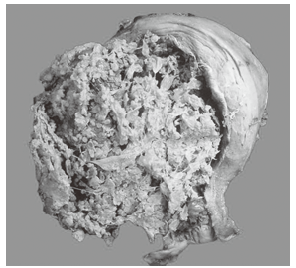

1. 肉眼观察 见大部分纤细分支的绒毛水肿,形成大量成串的半透明水泡;病变局限于子宫腔内,不侵入肌层。内含清亮液体,有蒂相连,状似葡萄(如图)。如果所有绒毛均呈葡萄状,称为完全性葡萄胎。部分绒毛呈葡萄状,仍保留部分正常绒毛,伴有或不伴有胎儿或其附属器官者,称为不完全性或部分性葡萄胎。绝大多数葡萄胎发生于子宫内,个别患者也可发生在子宫外异位妊娠的所在部位。